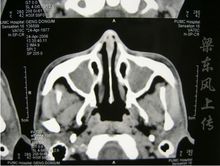

大部分患者以上呼吸道病變為首發症狀。通常表現是持續地流鼻涕,而且不斷加重。流鼻涕可來源於鼻竇的分泌,並導致上呼吸道的阻塞和疼痛。伴有鼻黏膜潰瘍和結痂,鼻出血、唾液中帶血絲,鼻竇炎(圖1)可以是緩和的,嚴重的GPA鼻中隔穿孔,鼻骨破壞,出現鞍鼻(圖2)。咽鼓管的阻塞能引發中耳炎,導致聽力喪失。而後者常是患者的第一主訴。部分患者可因聲門下狹窄出現聲音嘶啞,及呼吸喘鳴(圖3)。